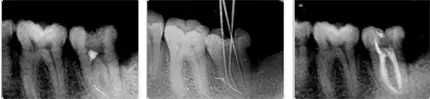

根管治療是在我們(men) 牙齒內(nei) 部進行的治療,清除根管位置的腐壞組織,從(cong) 病源開始處理口腔問題,保留**的原牙。通常都不是一次性能完成治療的,要依據**的牙齒情況。

醫生提醒,一般來說,根管治療需要做3到4次,醫生醫師會(hui) 根據**的情況,分步驟進行,**幫助**達到治愈的目的。我院顯微鏡下根管治療技術,配合專(zhuan) 業(ye) 醫師的熟練操作,全過程操作,您不用擔心治療中出現不適。